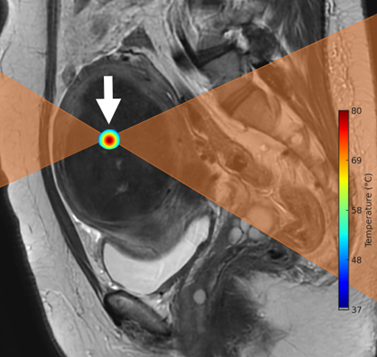

| 治療方法示意圖:

超音波能量聚焦在子宮肌瘤上(箭頭所示),術中會監測病灶內的溫度變化,確保能量到達可使組織壞死的溫度。